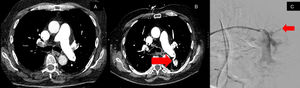

The patient returned to the hospital a day after discharge with hemoptysis, described as a quarter-sized dark red blood clot, occurring about four days post-thrombectomy. A computed tomography (CT) angiogram of the chest compared with the pre-thrombectomy CT chest (Fig. 1A), revealed a significant reduction in pulmonary arterial clot burden. However, a new finding was noted: a heterogeneously hyperdense structure in the superior left lower lobe, appearing connected to a left lower lobe segmental pulmonary artery (Fig. 1B). These findings were consistent with a pulmonary artery pseudoaneurysm. The patient underwent a pulmonary artery arteriogram, which confirmed the presence of the pseudoaneurysm. Following this confirmation, coil embolization was performed, with successful coiling verified fluoroscopically (Fig. 1C). After the procedure, the patient did not experience any recurrent episodes of hemoptysis and recover well.

A – demonstrates a CT image pre-thrombectomy without a pulmonary pseudoaneurysm. B – displays a CT image revealing a new heterogeneously hyperdense structure in the superior left lower lobe measuring up to 1.9cm×2.9cm, which appears to demonstrate connection to a left lower lobe segmental pulmonary artery concerning for a pulmonary pseudoaneurysm. C – pulmonary angiography with embolization of superior left lower lobe segmental pulmonary artery with coil.